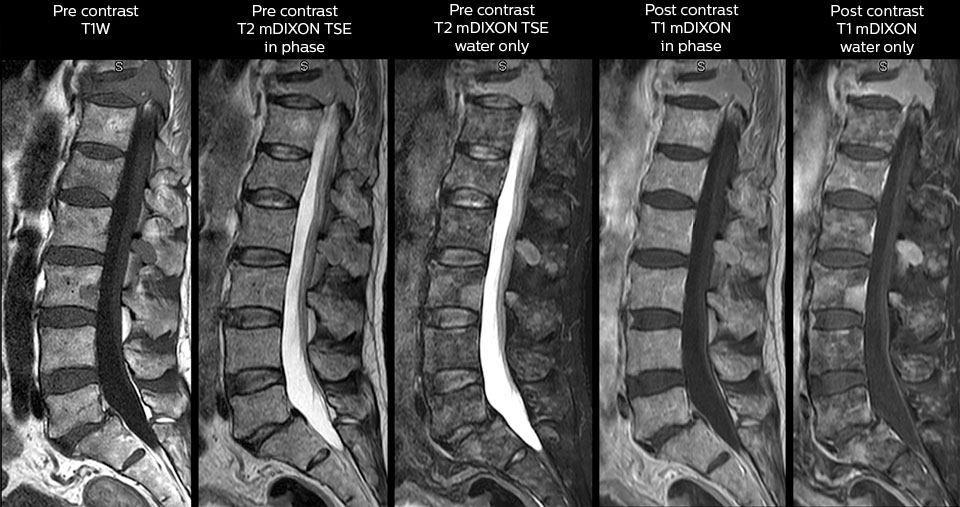

in image acquisition and postprocessing algorithms.”“mDIXON TSE sequences allow simultaneous characterization of morphological changes from the in-phase T2-weighted images and visualization of edematous changes, thanks to the water T2-weighted images from the same acquisition. Anatomical and morphological considerations could be a partial or complete ligament tear, a bony avulsion or hematoma.” “For soft tissue assessment mDIXON brings similar benefits. For example in one T2-weighted mDIXON TSE acquisition, having the multiple contrasts helps us assess abnormalities in peripheral nerves fascicles, which may be due to anatomical or inflammatory changes..” “In peripheral joints, we get good image quality in difficult areas with mDIXON TSE. Fat suppressed images appear homogeneous over the entire image, even with large coverage at 3.0T – for instance in scapular or hip girdles – or in the bearing areas or around metal prostheses*, where fat suppression is often deficient with STIR or spectral fat suppression, causing diagnostic difficulties. If a diagnostic image is right the first time, we don’t need to repeat or add a sequence.” “mDIXON TSE sequences allow simultaneous characterization of morphological changes from the in-phase T2-weighted images and visualization of edematous changes, thanks to the water T2-weighted images from the same acquisition. Anatomical and morphological considerations could be a partial or complete ligament tear, a bony avulsion or hematoma.” “For soft tissue assessment mDIXON brings similar benefits. For example in one T2-weighted mDIXON TSE acquisition, having the multiple contrasts helps us assess abnormalities in peripheral nerves fascicles, which may be due to anatomical or inflammatory changes..”

To minimize the time taken to perform scans, rapid MRI examination protocols (ExamCards) were developed, shortening the total scanning time to even less than 10 minutes in some exams. Techniques like mDIXON (modified DIXON) are used for robust capturing of fat-free MRI images in a hectic ED environment.